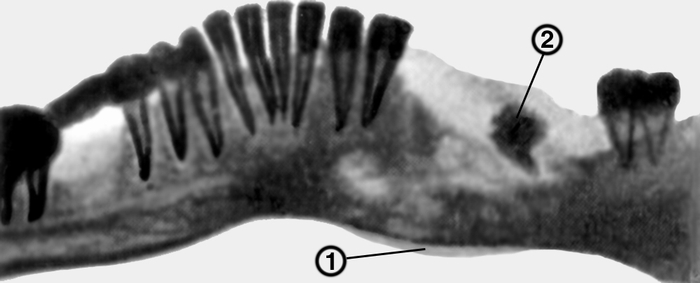

Рентгеновские снимки посттравматического остеомиелита челюсти: Медицинские случаи

Раздел: Образы вокруг